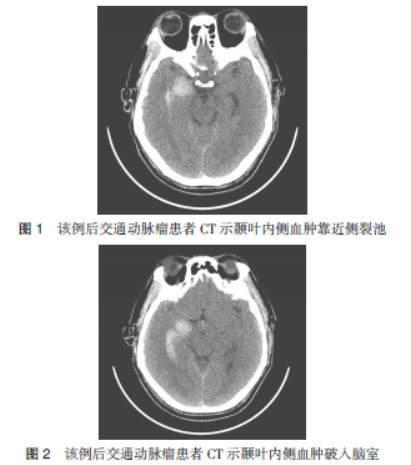

以颞叶出血并破入脑室为首发CT表现的后交通动脉瘤一例并文献复习

病史摘要:男性患者,因突发头痛、头晕2天入院,自服药物症状未改善。既往有糖尿病及冠心病史。诊疗过程:入院查体神志清、颈部稍抵抗等。头部CT示脑出血破入脑室,CT动脉造影显示右侧后交通动脉瘤。家属同意后于入院第3天手术,术中放置脑室外引流,夹闭瘤颈及后交通动脉,术后给予预防血管痉挛、感染等治疗,住院17天出院,随访3个月恢复良好。情况总结:该病例的主要价值在于以颞叶出血并破

动脉瘤

疑难